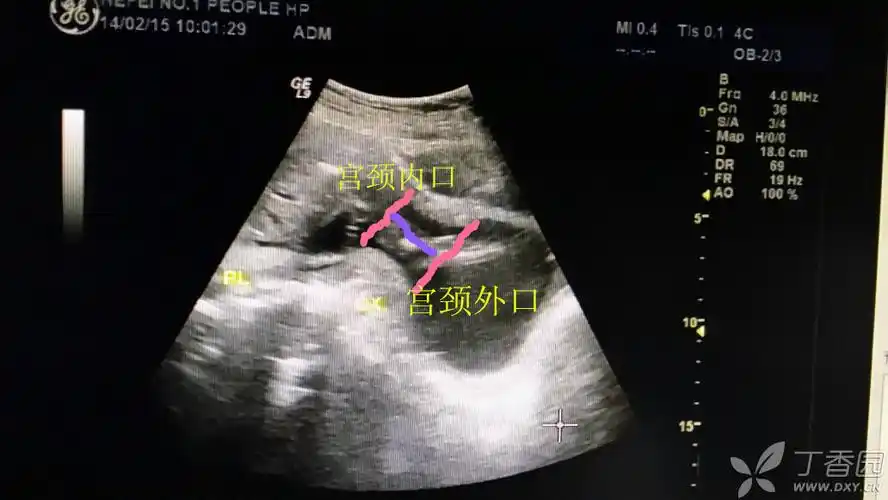

我试着帮你测量,紫线应该就是宫颈的长度